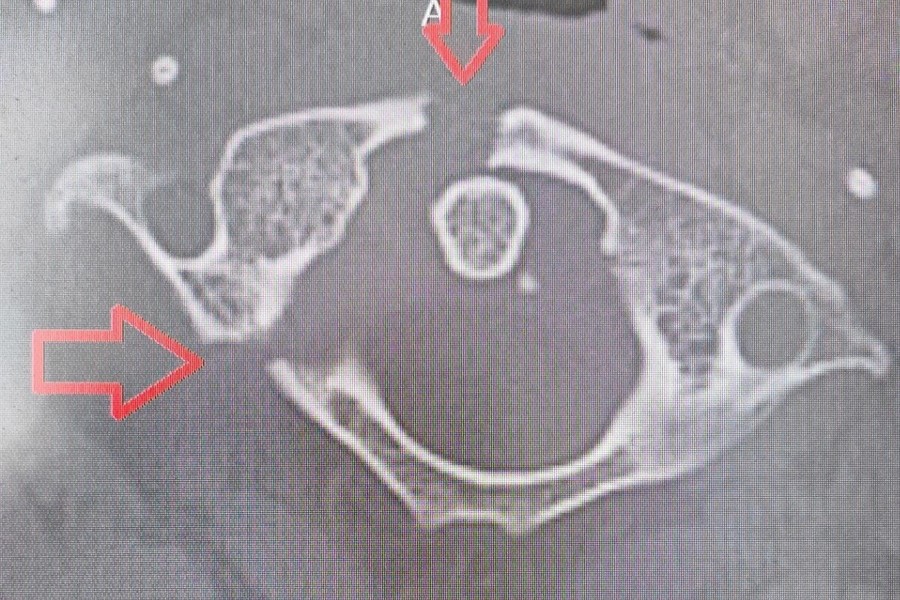

Двое парней получили травмы в бассейне. Один поскользнулся и упал в воду, получив перелом и вывих пятого шейного позвонка. Другой нырнул и ударился головой, что привело к трещине в первом шейном позвонке. Третий молодой человек отличился — он упал с турника. Обследование показало повреждение третьего шейного позвонка.

В каждом случаев пострадавшим потребовалось установить металлоконструкцию для стабилизации. Неделю пациенты провели в травматологическом отделении, после чего им назначили ношение специального корсета и отпустили долечиваться домой.

Ныряльщику с поврежденным первым шейным позвонком установили систему гало-фиксации. С этой конструкцией ему предстоит ходить до трех месяцев.